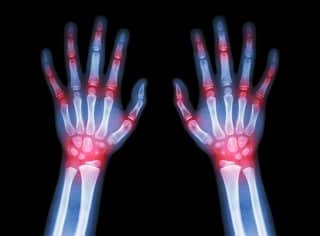

Rheumatoid Arthritis Special: Exploring the Latest Advancements and Patient Care Trends in Southwest Florida Read More »